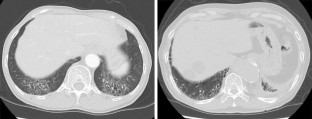

Fig. 1

Fig. 2

Fig. 3

Fig. 4